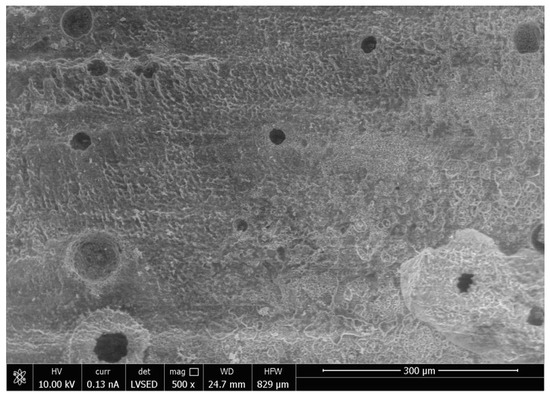

SEM analysis of the abutment teeth demonstrated rotary cutting streaks on the tooth surface at a low magnification of 500× (Figure 5). At higher magnifications (≥5000×), there were more openings of the dentinal tubules observed in the rotary handpiece removal group compared to the laser group. The dentin surface of the specimen from laser crown removal appeared to have a more intact smear layer and residual cement (Figure 6A,B). Crown specimens from the rotary group presented with more crack and crest lines at higher magnification levels (10,000×), indicating possibly more surface damage of the ceramic material compared to the laser group (Figure 7A,B).

Thermal stimulation of pulp tissue can occur during crown removal using both the laser and air rotary handpiece techniques. An increase in pulpal temperature by over 5.6 °C is thought to induce pulpal damage [25,26,27] and a pulpal temperature of over 42 °C can cause increased blood flood into the pulp or pulpal hyperemia, resulting in irreversible pulp damage [28]. Increases in pulpal temperature during removal with either the laser or rotary handpiece technique did not exceed 27.7 °C and the temperature change for both methods is less than 2–3 °C. Laser irradiation also showed more variation in temperature and higher temperature readings compared to air rotary removal. Differences in increases in pulpal temperature can be attributed to the functionality of each device. Higher temperature readings associated with laser irradiation can be attributed to longer procedure times, less water spray for cooling, and higher energy needed for crown removal. When crowns are removed with an air rotary handpiece, the energy is absorbed on the surface of the crown and further away from the pulp. Laser energy is absorbed by the underlying chromophore (cement), which is closer in proximity to the pulpal tissue, and thus contributes to greater increases in pulpal temperature during laser crown removal. Primary anterior teeth have a thin layer of remaining dentin that overlies the pulp chamber following tooth preparation, thus the higher temperature change in this group during laser irradiation can probably be attributed to the thin dentinal layer between pulp and luting cement. Adequate water spray is essential to prevent thermal damage to pulpal tissues. Thinner dentin and larger pulpal chambers, especially in pediatric permanent teeth, may be prone to thermal irritation during laser irradiation [29]. The small anatomical primary tooth crown can also be a factor. Thus, it may be preferable to decrease laser setting parameters in the pediatric population, which may lengthen the time required for crown debonding. Pulpal irritation can also be caused by the direct irritation of the dentinal tubules. The SEM analysis of an abutment tooth in the rotary handpiece group revealed greater opening of the dentinal tubules compared to the laser group. The laser removal method appeared to leave a smear layer and cement layer covering the dentin surface that was not apparent in the rotary handpiece group. Greater amounts of open dentinal tubules and lack of a smear layer can result in a higher possibility of post-operative sensitivity following crown removal.

Similar to previous studies, crown removal by laser does not appear to damage the retrieved crowns or the underlying tooth structure [3,6,18,30]. In our study, SEM analysis demonstrated that laser irradiation of zirconia crowns showed no underlying tooth damage and fewer surface irregularities of the crown surface compared to air rotary removal. Evidence of changes in tooth structure at low magnification following removal with a rotary handpiece proves there is a risk of damaging the tooth during crown removal. However, if a crown was to be retrieved due to recurrent caries, then the extent of the caries will impact the dentin surface and smear layer, irrespective of what crown removal technique is employed.

Figure 6. Scanning Electron Microscope Image of the Surface of the Tooth at Magnification 5000× Following Crown Removal with Rotary Handpiece (A) and Er,Cr:YSGG Laser (B).